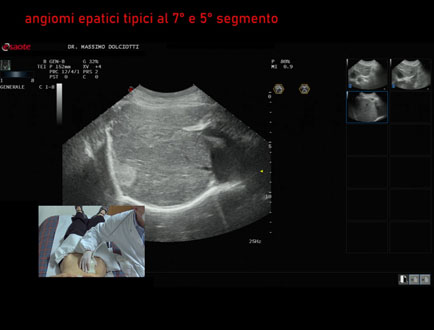

Motivazione dell'esame: dolori ipocondrio destro, follow up per angiomi epatici

Commento all'esame: le immagini ed il video documentano 2 immagini iperecogene, la maggiore al settimo segmento epatico sottodiaframmatica, delle dimensioni di 27x20 mm, da ricondurre ad angioma epatico tipico. Formazione simile, di dimensioni minori, al quinto segmento epatico.

Conclusioni: angiomi epatici tipici al 7° e 5° segmento (typical hepatic hemangiomas in the 7th and 5th segments).